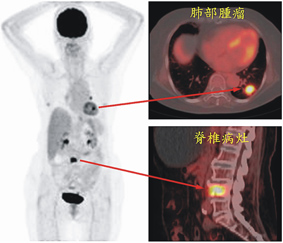

▲ 圖一、箭頭處所示腫瘤部分呈現明顯代謝升高現象,配合斷層掃描可得功能及結構性生物影像

▲圖二、此病患最近半年飽受體重減輕及下背痛困擾,前來求診並進行健康檢查。

正子電腦斷層掃描發現除了在後背疼痛處發現高葡萄糖代謝骨骼病灶之外,另外也在左肺發現有呈現葡萄糖攝取增加的肺部腫瘤及肺門淋巴結。根據正子掃描的結果,顯示可能是惡性腫瘤併發轉移的現象。